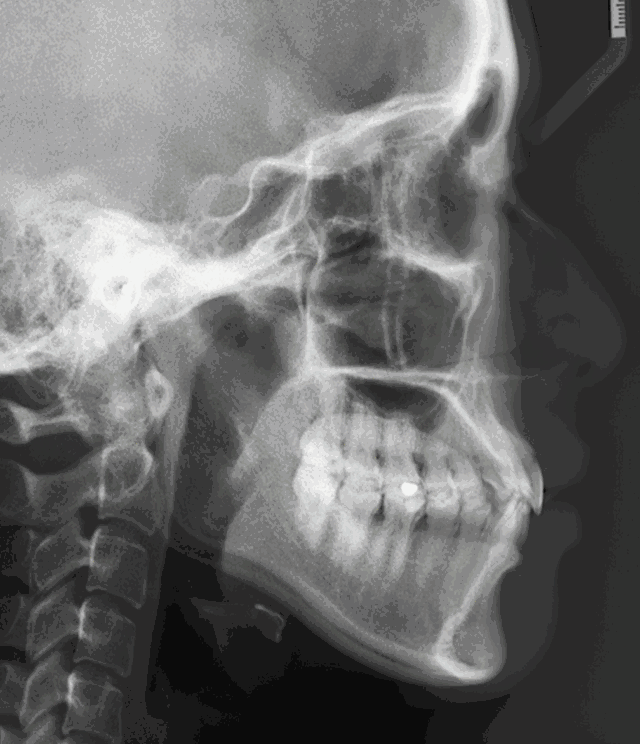

那么,怎么樣判斷嘴凸是骨性還是牙性?一眼讓你看明白!

【骨性突嘴和牙性凸嘴判斷對(duì)比圖】:↓↓

骨性突嘴和牙性凸嘴判斷對(duì)比圖

郭醫(yī)生表示,嘴凸牙性和骨性的區(qū)別在于,

單純的牙性突嘴,僅有牙齒向前突,?

牙齒長(zhǎng)軸角度傾斜過(guò)大,上唇和鼻子周圍是不鼓的。

而骨性突嘴,牙齒的上頜骨,還有鼻子周圍都是向前鼓的,

并且露出的牙齒比較多,從面相上來(lái)看,嘴唇是包不住牙齒,

骨性齙牙在笑的時(shí)候很明顯,有些整顆牙齒和牙齦會(huì)露出來(lái)。